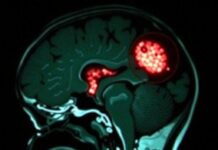

- МРТ (магнитно-резонансная томография) — показывает воспалённые участки мозга и помогает отличить энцефалит от других заболеваний.